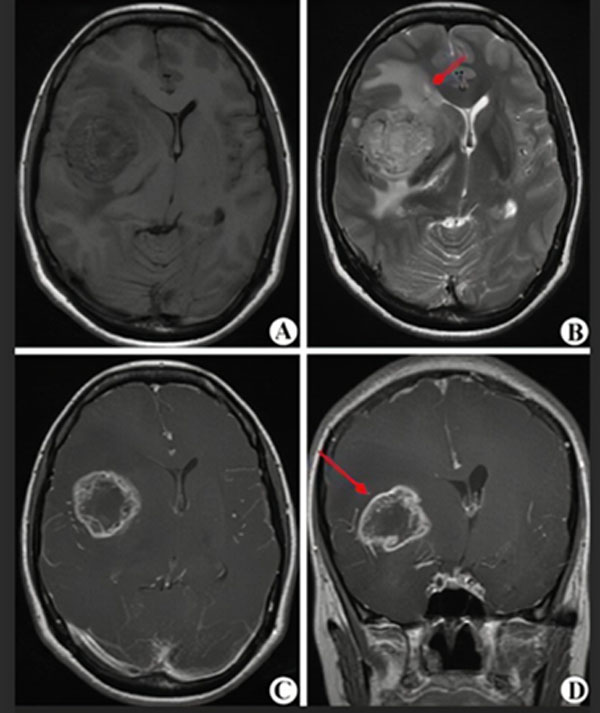

MRI(核磁共振)是一种无创伤的影像学检查,对脑肿瘤敏感性较高,大约1-2天可以拿到结果,是诊断和评估治疗效果的首选。但准确性只有80%-90%,不能作为确诊的最终依据。

(图A-D显示为高级别胶质瘤的核磁表现,红箭头指示肿瘤所在)